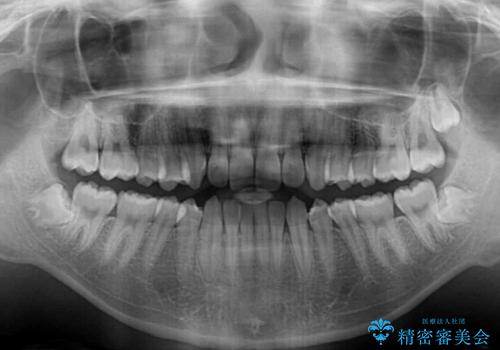

- 上下前歯のデコボコを気にして来院された患者様です。

入試時期に入ると、後戻り防止のリテーナー装着が疎かになる可能性があったり、リテーナーが壊れてしまった場合すぐに来院できなかったりというリスクがあったため、下顎前歯の舌側をワイヤーで固定することとしました。